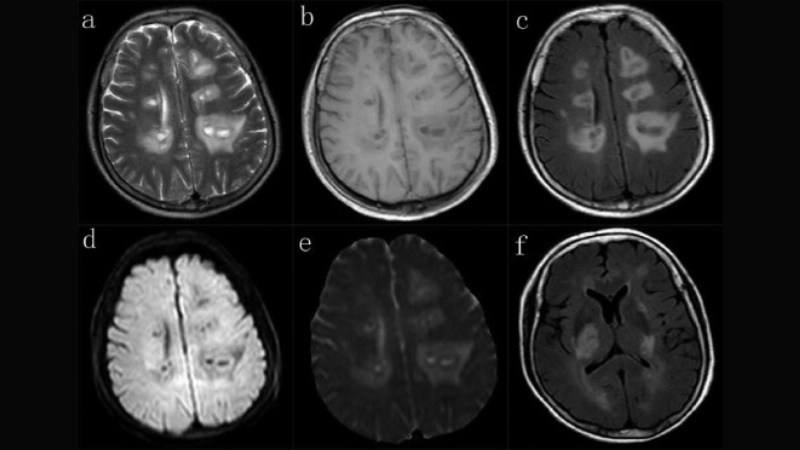

Image description of Viral Encephalitis

Encephalitis diagnosis requires imaging and lab tests